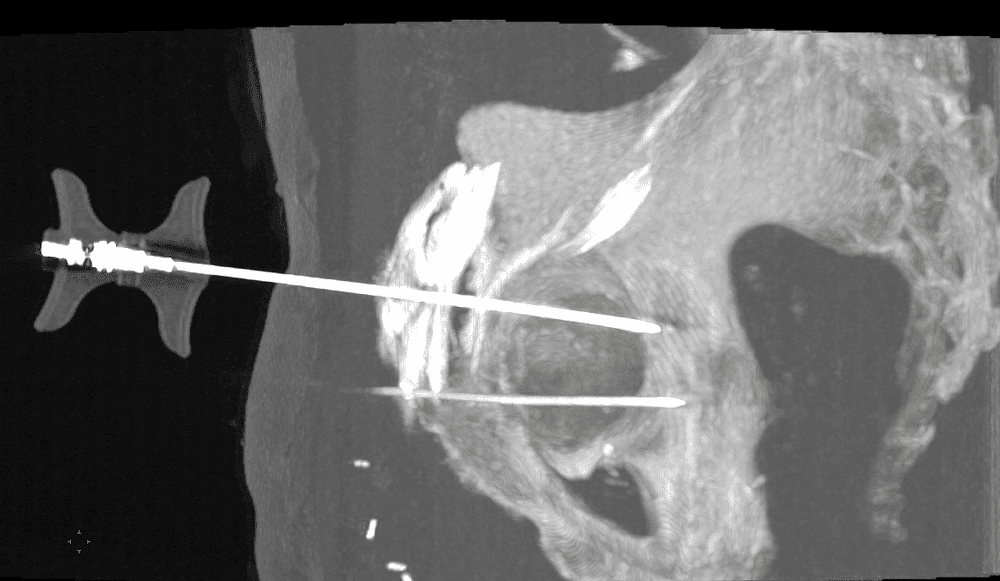

Technique de vissage percutané des fractures du toit du cotyle